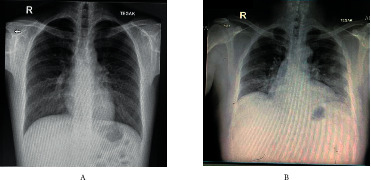

Figure 2.

Chest X-rays of the patients. (a) Chest X-ray revealed a typical COVID-19 radiological appearance of diffuse infiltrate at the base, which extended to the periphery of the lungs. (b) Chest X-ray revealed a typical COVID-19 radiological appearance of basal nodular infiltrate at the periphery of the lungs, especially dominant in the left side.

The first patient, a 24-year-old man, presented to the emergency department (ED) of Cipto Mangunkusumo Hospital (RSCM) with the chief complaint of fever which had been present for one day. Notable symptoms upon diagnosis were coughing, rhinorrhea, nasal congestion, and fever. There was no dyspnea, but dysgeusia and anosmia developed on the second day of admission. There were no comorbidities such as obesity or underlying pulmonary disease. The patient was found to have received the first and second doses of CoronaVac 19 days and 5 days prior to the onset of symptoms, respectively. Physical examination revealed normal vital signs, and lung examination demonstrated coarse rales, dominant in the lower left lung. Upon admission, the patient had a hemoglobin level of 14.8 g/dl, leukocyte count of 7.010/µl, and platelet count of 258.000/µl. The patient had a D-dimer level of 210 µg/l and fibrinogen level of 271 mg/dl, with CRP and procalcitonin levels of 115 mg/l and 0.04 ng/ml, respectively. Laboratory examinations revealed SARS-CoV-2 PCR positive with RdRP Cq of 17.70, E-gene Cq of 17.27, and N-gene Cq of 16.65. Chest X-ray revealed a typical COVID-19 radiological appearance of diffuse infiltrate at the base which extended to the periphery of the lungs.

The second patient, a 49-year-old man, came with the chief complaint of fever. The fever was present for 3 days and had started 11 days before admission, ranging from 37.7–38.0°C. The fever started on the same day when the patient received his vaccination. There was unproductive cough, and anosmia and dysgeusia developed on the same day with the fever onset. Diarrhea occurred 1 day before presentation to the hospital. The patient also had longstanding hypertension and diabetes mellitus without regular checkups or medications. At presentation, the patient was hypertensive, with a blood pressure of 190/80 mmHg. There were no rales or other physical abnormalities upon physical examination. Laboratory examination revealed hyperglycemia, hyponatremia hypoosmolar euvolemia, and hypokalemia. Procalcitonin was 0.08 ng/ml and CRP was 79.2 mg/l, while fibrinogen and D-dimer levels were 678.4 mg/dl and 380 µg/l, respectively. Chest X-ray revealed a typical COVID-19 radiological appearance of basal nodular infiltrate at the periphery of the lungs, especially on the left side. Electrocardiography (ECG) revealed a complete right bundle branch block (RBBB). SARS-CoV-2 PCR on the admission day was positive with RdRP Cq of 28.27, E-gene Cq of 27.83, and N-gene Cq of 27.28. The timeline of vaccination and disease manifestation of both patients and chest X-ray are presented in Figures 1 and 2 respectively. Both patients had almost similar levels of S-RBD protein titers of 18 and 15 U/ml. Complete laboratory data of the patients can be found in Supplemental Data 1.